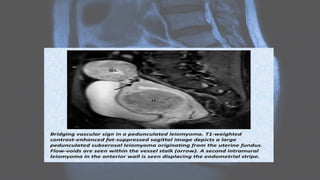

MRI

Uterine leiomyomas • Uterineleiomyomas, also known as uterine fibroids, are benign tumors of myometrial origin and are the most common solid benign uterine neoplasms. They are a common incidental finding on imaging and rarely cause diagnostic dilemma. Plain radiograph • Popcorn calcification within the pelvis may suggest the diagnosis.

CT • fibroids areusually seen as soft tissue density lesions and may exhibit coarse peripheral or central calcification • they may distort the usually smooth uterine contour • enhancement pattern is variable